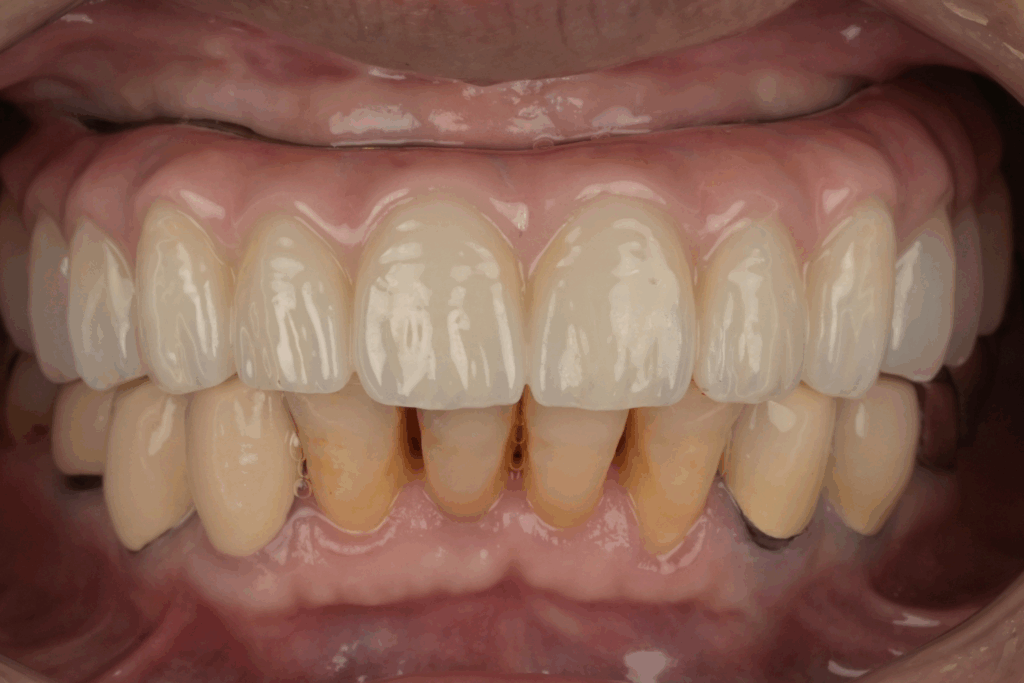

案例3. 上顎+下顎All on X

Before

After